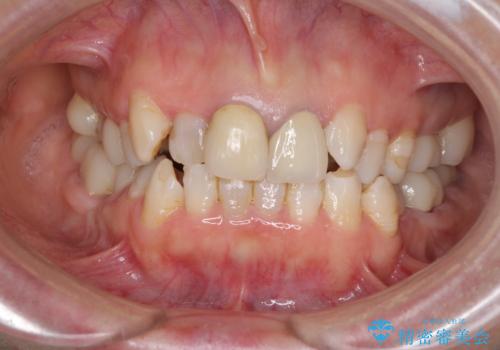

- 全顎的な歯列不正と、銀歯だらけの奥歯を気にして来院された患者様です。

奥歯の銀歯は、セラミッククラウンを装着するには歯の高さが不十分であり、そのままでは矯正治療を行うことが困難であるため、歯冠長延長術を行うこととしました。

また、根管治療の必要な歯がいくつかあるため、歯周外科治療の治癒期間を利用して根管治療を行い、その後インビザラインにて矯正治療を行うこととしました。

矯正治療後にはオールセラミッククラウンにて補綴治療を行うこととしました。